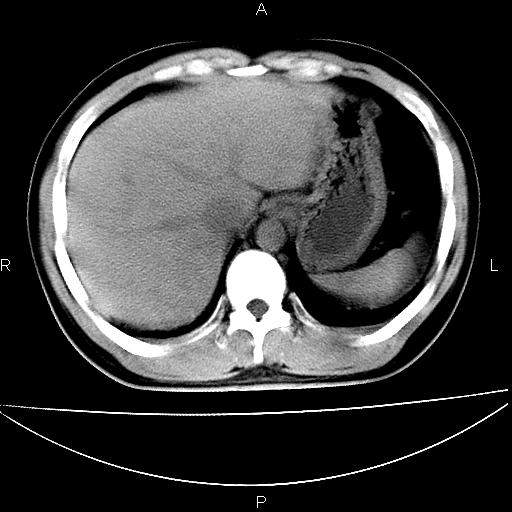

男 25岁 自述 尿频尿急,排尿困难20多天.无腰痛, b超说左肾盂轻度积水,左输尿管上端扩张.未见结石影. ct我看双侧肾盂轻度积水,双输尿管上端都扩张,大家看看能看见结石吗?

双肾轻度积水,双侧输尿管上段扩张(原因待查)。

双输尿管扩张下端未见高密度结石和输尿管晕轮征,不好说是结石.增强后如何?

双肾轻度积水,未见明确结石,薄层对结石检出率较高。

双肾盂及双输尿上段轻度积水,双输尿管未见明显结石影。